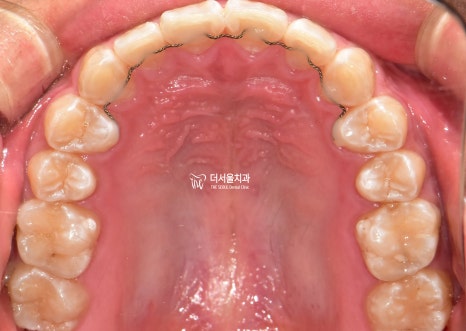

구강 사진을 보면

윗니가 뻐드러져 있는 걸 볼 수 있으며

아랫니는 치열이 고르지 못한 것을 알 수 있었습니다.

전체적으로

문제점을 종합해 보면

2급 부정교합과 과개 교합을 나타내고 있었습니다.

인비절라인 후

구내 사진을 보여드리겠습니다

고르지 못했던 치열도

바르게 개선되면서 ‘U’ Shape를 나타냈으며

안쪽 면에 설측 유지 장치를 붙여드리게 되었습니다.